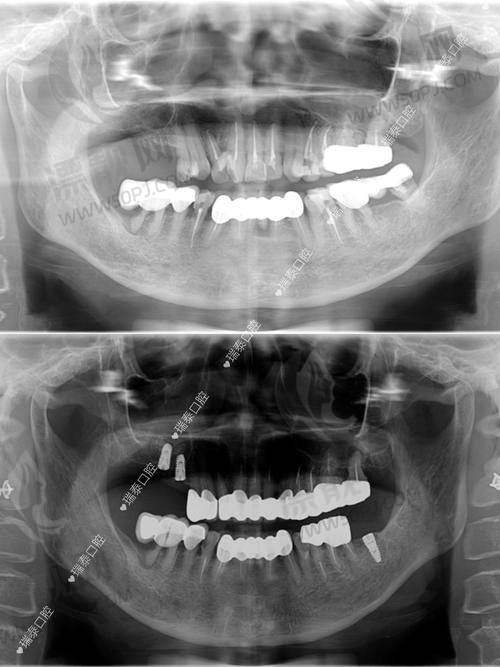

1)数字化种植牙技术:采用德国卡瓦(Kavo)设备,3D影像辅助下进行数字引导种植,听起来就高大上。

根据官网与实地拍摄显示:科瓦使用的设备大多为进口品牌,如德国Kavo牙椅、3Shape口扫系统、西诺德CT机,部分门店还建有“数字化种植中 心”,但不同门店配置会略有不同。